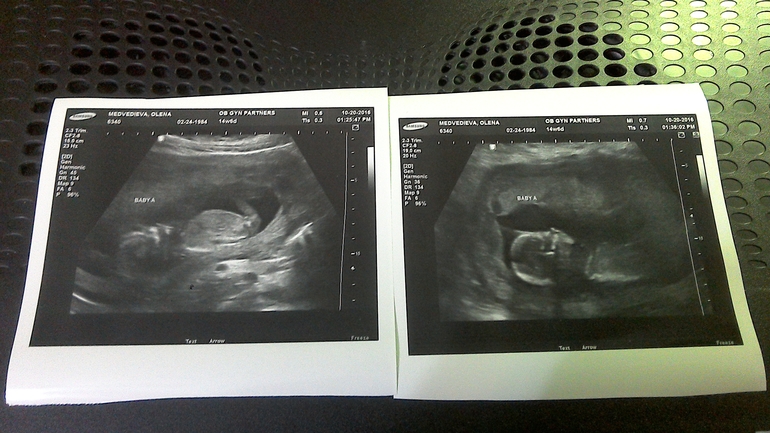

15 недель УЗИ

Всё о нашей беременностиПрилетела я из РФ, долетела хорошо, только устала. Отдохнула с десяток дней и вот сегодня наконец то первое УЗИ в США и первый приём у врача. Встала на учет. У нас все хорошо, развиваемся тоже хорошо. Весим уже чуть больше чем по 110г. уже тяжеленькие крошки. Папа доволен, бабушка и дедушка тоже! Даже кот спит со мной! Вот фоточки!

Беби А